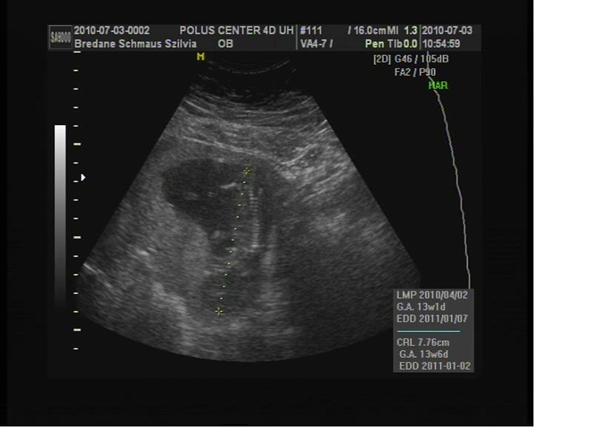

2010.07.03 18:37

2010.07.03 19:59

Erős vagyok,én tartom a placentát!!!

Erős vagyok,én tartom a placentát!!!  Ekkora vagyok már!

Ekkora vagyok már!2010.07.03 22:17